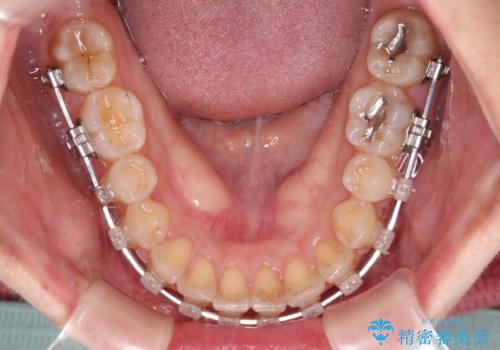

- クリアブラケット

- 1年7ヶ月

舌の突出癖により上下前歯が開咬となりましたが、舌のトレーニングと顎間ゴムの使用により、元々の被蓋関係に改善することができました。

アンカースクリューを用いて、出っ歯仕上がりを回避し、正中位置も改善することができました。